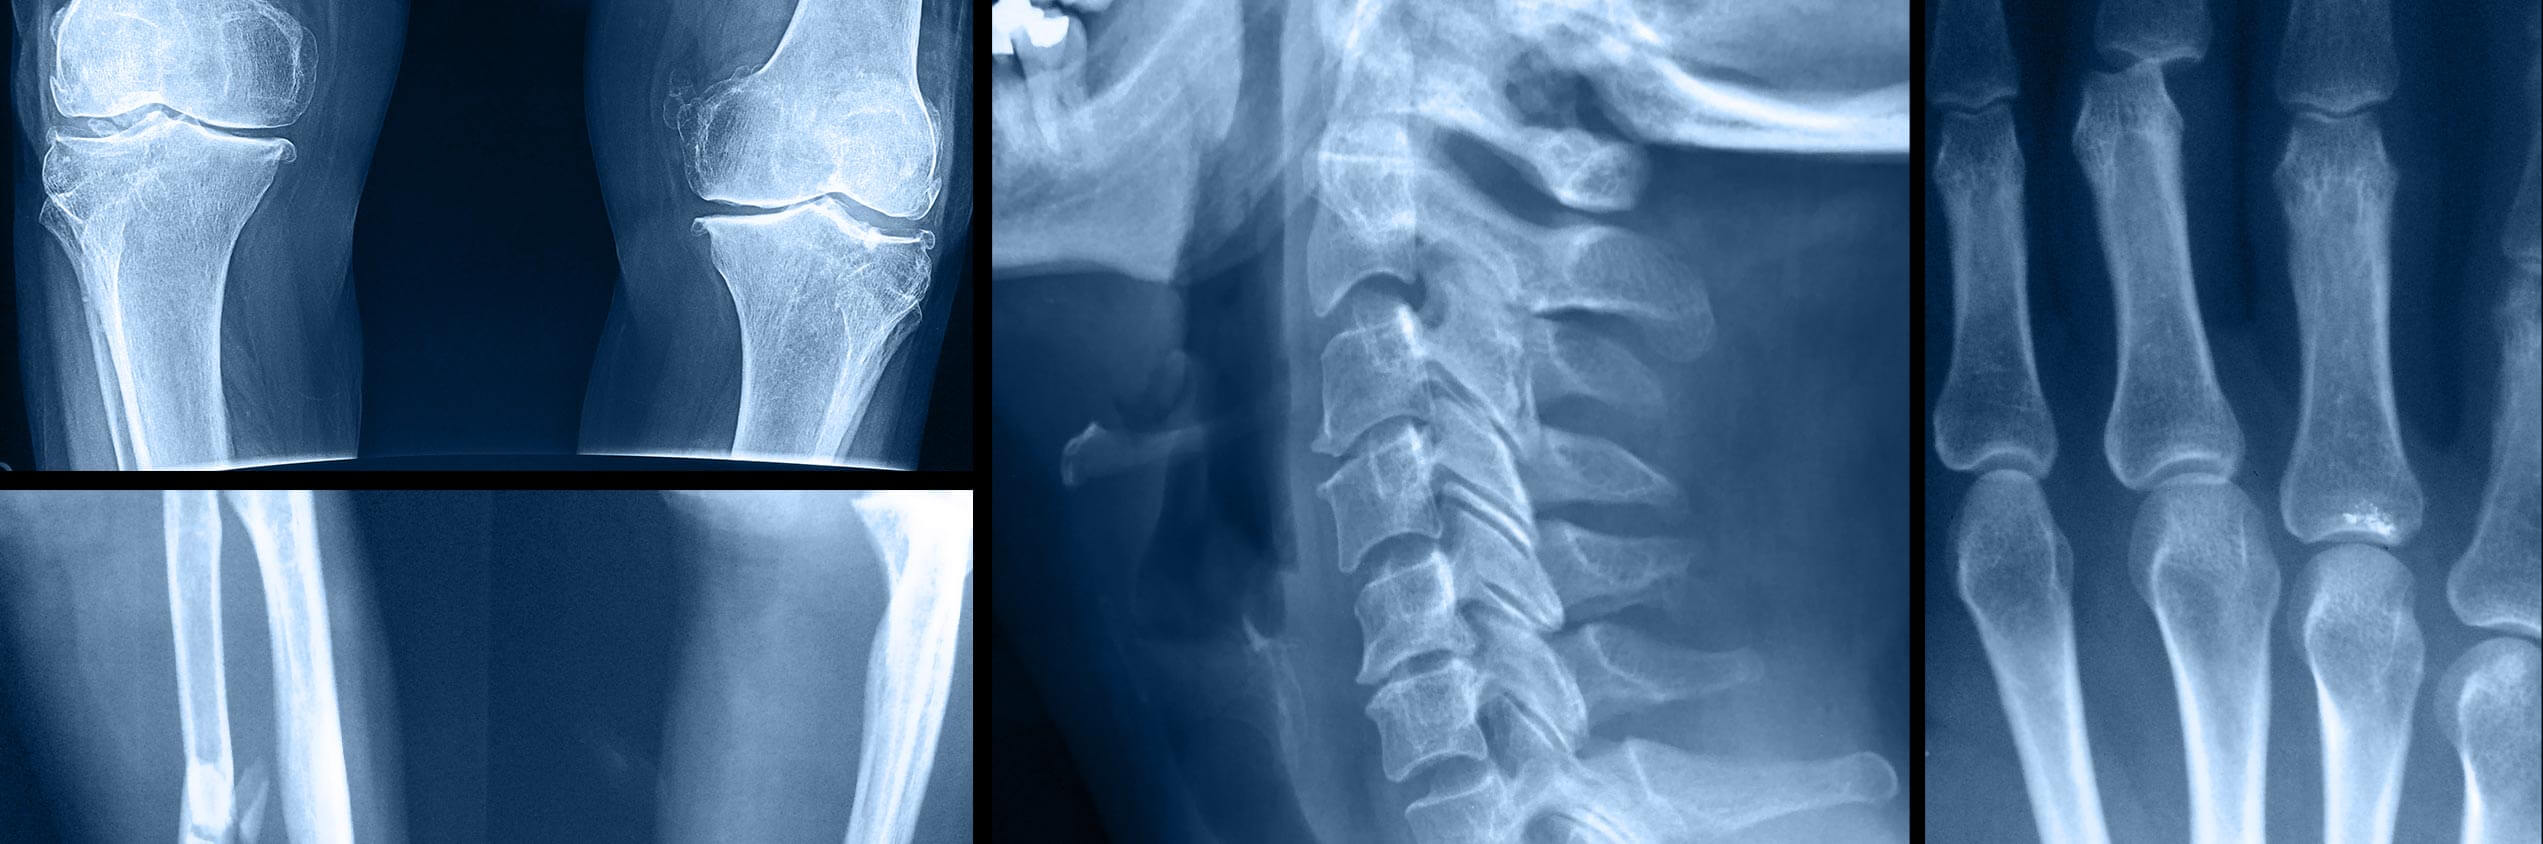

Orthopaedic Surgery deals with the musculoskeletal system; the bones, joints, ligaments, tendons, muscles and nerves that keep people moving. Orthopaedic surgeons are Medical Doctors (MD) or Doctors of Osteopathic Surgery (DO) who may be certified by the American Board of Orthopaedic Surgery or the American Osteopathic Board of Orthopaedic Surgery.

List of All Orthopaedic Specialists at UnaSource Surgery Center